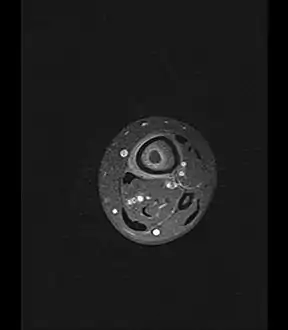

Axial T1-weighted MRI pre-contrast enhancement showing that the intramedullary collection is T1-hyperintense suggesting proteinaceous viscous fluid consistent with infection. Axial T1-weighted MRI pre-contrast enhancement showing that the intramedullary collection is T1-hyperintense suggesting proteinaceous viscous fluid consistent with infection.

Axial T1-weighted fat-saturated MRI image following IV gadolinium contrast demonstrating the intramedullary lytic area seen on radiography to be ring enhancing consistent with a purulent fluid collection. Extensive circumferential periosteal enhancement is noted. There is also substantial bone marrow enhancement. Axial T1-weighted fat-saturated MRI image following IV gadolinium contrast demonstrating the intramedullary lytic area seen on radiography to be ring enhancing consistent with a purulent fluid collection. Extensive circumferential periosteal enhancement is noted. There is also substantial bone marrow enhancement.